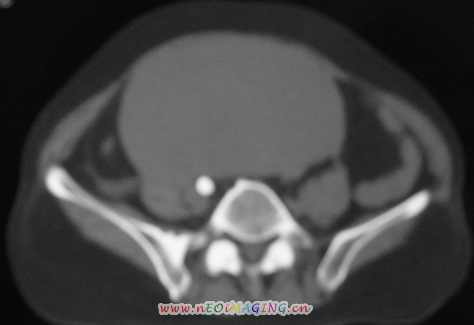

标题: CT11527:女56岁以右输尿管结石入院

女56岁以右输尿管结石入院

病灶位于下腹部盆腔,从子宫与膀胱明显受压后移看,应该来源于盆腹腔的占位,病灶实性部分密度均匀,左侧可见低密度灶,建议增强扫描,考虑:间叶性肿瘤,或硬纤维瘤,输尿管下段结石伴上段输尿管扩张

1)盆腔占位性病变,考虑来源于卵巢,囊腺瘤可能性大。2)右侧输尿管第二狭窄处结石伴梗阻。

今天病人已经手术证实为右附件囊肿,右侧输尿管第二狭窄处结石伴梗阻!!!

[病理诊断] CT11527:右附件囊肿,右侧输尿管结石。